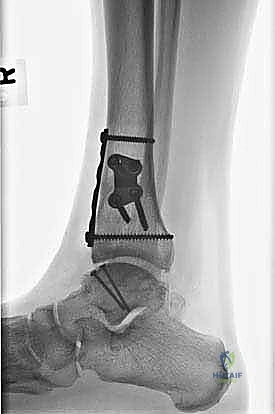

- التصوير بالأشعة السينية (X-rays): الخطوة الأولى لاستبعاد الكسور الكبيرة وتقييم المحاذاة العامة للعظام. قد تظهر الأشعة السينية الآفات الكبيرة، لكنها غالباً ما تفشل في إظهار التلف الغضروفي المبكر.

- التصوير المقطعي المحوسب (CT Scan): ضروري جداً للآفات الكبيرة. يوفر الـ CT صورة ثلاثية الأبعاد للعظم، مما يساعد الجراح في التخطيط الدقيق لعملية قطع العظم وحجم الطعم المطلوب زراعته.